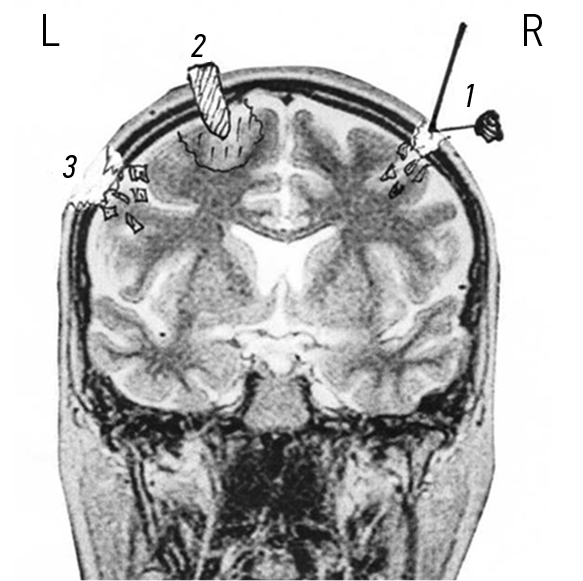

Ходы раневых каналов при огнестрельных проникающих осколочных ранениях черепа и ГМ, также примеры диагнозов продемонстрированы на рис. 3–7.

Рис. 5. Огнестрельные проникающие диаметральные ранения черепа и головного мозга. Примеры диагнозов: 1 — минно-взрывное ранение (МВР). Огнестрельное осколочное слепое (сквозное) проникающее диаметральное ранение лобных долей головного мозга; 2 — МВР. Огнестрельное осколочное слепое (сквозное) проникающее диаметральное ранение левой лобной и правой теменной долей головного мозга; 3 — МВР. Огнестрельное осколочное слепое (сквозное) проникающее диаметральное ранение левой теменной и правой лобной долей головного мозга; 4 — МВР. Огнестрельное осколочное слепое (сквозное) проникающее диаметральное парамедианное ранение правой лобной, теменной и затылочной долей головного мозга; 5 — МВР. Огнестрельное осколочное сквозное проникающее незавершенное диаметральное ранение правой теменной и левой лобной долей головного мозга.

Рис. 6. Огнестрельные проникающие диагональные и парабазальные ранения черепа и головного мозга. Примеры диагнозов: 1 — минно-взрывное ранение (МВР). Огнестрельное осколочное слепое (сквозное) проникающее переднее парабазальное ранение лобной доли головного мозга; 2 — МВР. Огнестрельное осколочное слепое (сквозное) проникающее диагональное ранение лобной доли головного мозга; 3 — МВР. Огнестрельное осколочное слепое (сквозное) проникающее диагональное ранение затылочной доли и полушария мозжечка; 4 — МВР. Огнестрельное осколочное слепое (сквозное) проникающее ранение затылочной доли, полушария мозжечка и ствола головного мозга; 5 — МВР. Огнестрельное осколочное слепое (сквозное) проникающее парабазальное ранение ствола головного мозга.